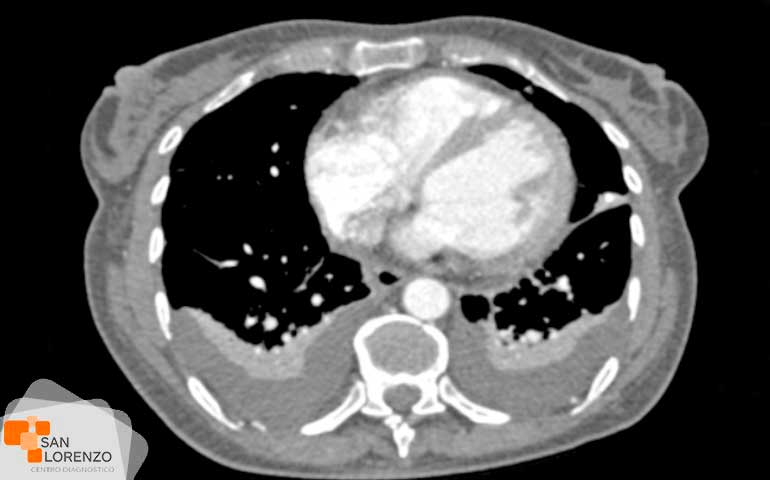

La tomografía computarizada o según sus siglas TAC o escáner, es un examen médico que se basa en la radiología entendiéndola como la emisión de rayos X para captar imágenes del cuerpo u órgano en diferentes planos. Entre sus aplicaciones diagnósticas al corazón, el cardio TAC o escáner al corazón, es un examen que utilizando un equipo y un sistema especial de rayos X, permite sacar diferentes imágenes de las arterias coronarias, detectando si están bloqueadas o angostadas por la acumulación de placa (un índice de aterosclerosis o enfermedad de las arterias coronarias). En el caso del examen score total de calcio coronario por tomografía computarizada (scanner) como también se le conoce comúnmente, permite no solamente cuantificar el calcio coronario. También permite entregar información valiosa sobre los vasos sanguíneos en el caso de la angiotomografía.

Las imágenes transversales que se pueden lograr durante el procedimiento de una TAC cardíaca, permite hoy en día lograr hoy en día diferentes planos, incluso imágenes tridimensionales. En el caso de la angiotomografía, y utilizando la misma tecnología diagnóstica operada por nuestro equipo clínico y médicos especialistas de centro de diagnóstico San Lorenzo. Permite que este procedimiento sea una opción valiosa desde el punto de vista de la información que puede ofrecer, pues utilizando un tinte especial o material de contraste, ofrece información sobre la forma en que fluye la sangre a través de las arterias, detalles de los vasos sanguíneos, y si existen obstrucciones en el flujo de sangre que va hacia el corazón.

En resumen, cabe decir que el examen de TAC cardíaca para la cuantificación de calcio coronario o angiografía coronaria por tomografía computarizada, es una técnica no invasiva que muestra la información importante de patologías de las arterias coronarias, sobre todo considerando que el calcio es buen marcador de enfermedades de acumulación de placa, y que dependiendo la cantidad presente, es un instrumento útil para pronosticar estas enfermedades relacionadas con la enfermedad de arterias coronarias (EAC).